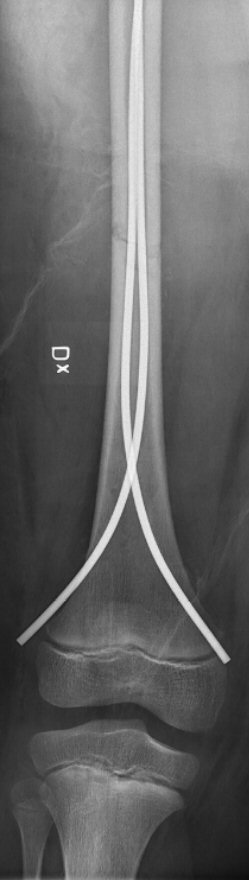

- Vikt > 20 kg: diafysär fraktur opereras ofta med TEN-spik. Man kan sätta in fler än två TEN-spikar för att få stabilare förhållanden.

Diafysär femurfraktur, fixerad med två TEN-spikar